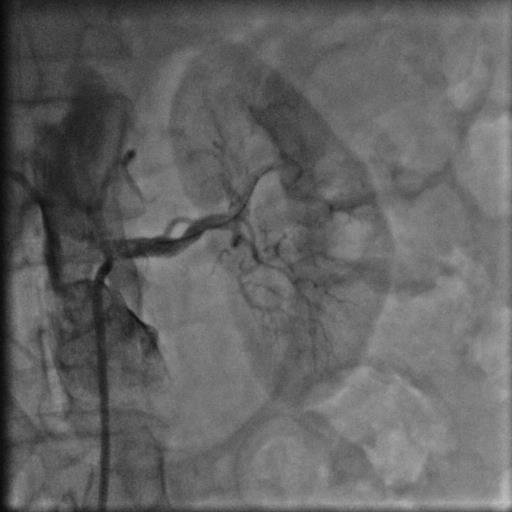

44 yaşında şeker hastalığı olan hastamız dirençli yüksek tansiyon şikayetiyle bize başvurdu. Herhangi bir sebep bulunamayan hastamız 2 yıldan beri cesitli ilaçlar kullanmasına rağmen tansiyonunun düşürülemediğini söylüyordu. Yaptiğımız detaylı muayene ve tetkikler sonucu böbrek damarının tıkalı olduğunu tesbit ettik ve yaptıgımız stent işlemi sonrasında hastamız normal tansiyon değerleriyle taburcu edildi..